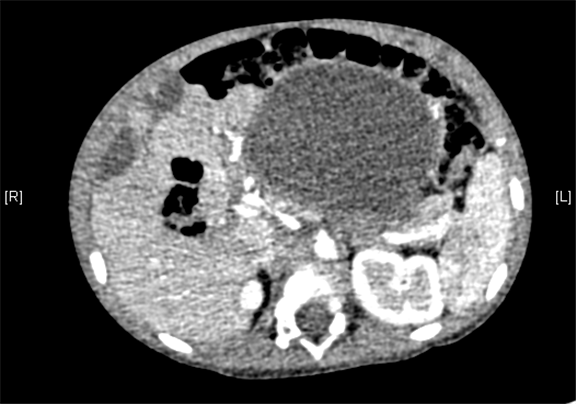

腹部三维动态CT:腹腔巨大囊性占位性病变,考虑肠系膜来源良性病变可能性大,腹腔肠系膜淋巴管瘤?

术前CT检查:

动脉期

静脉期

平衡期